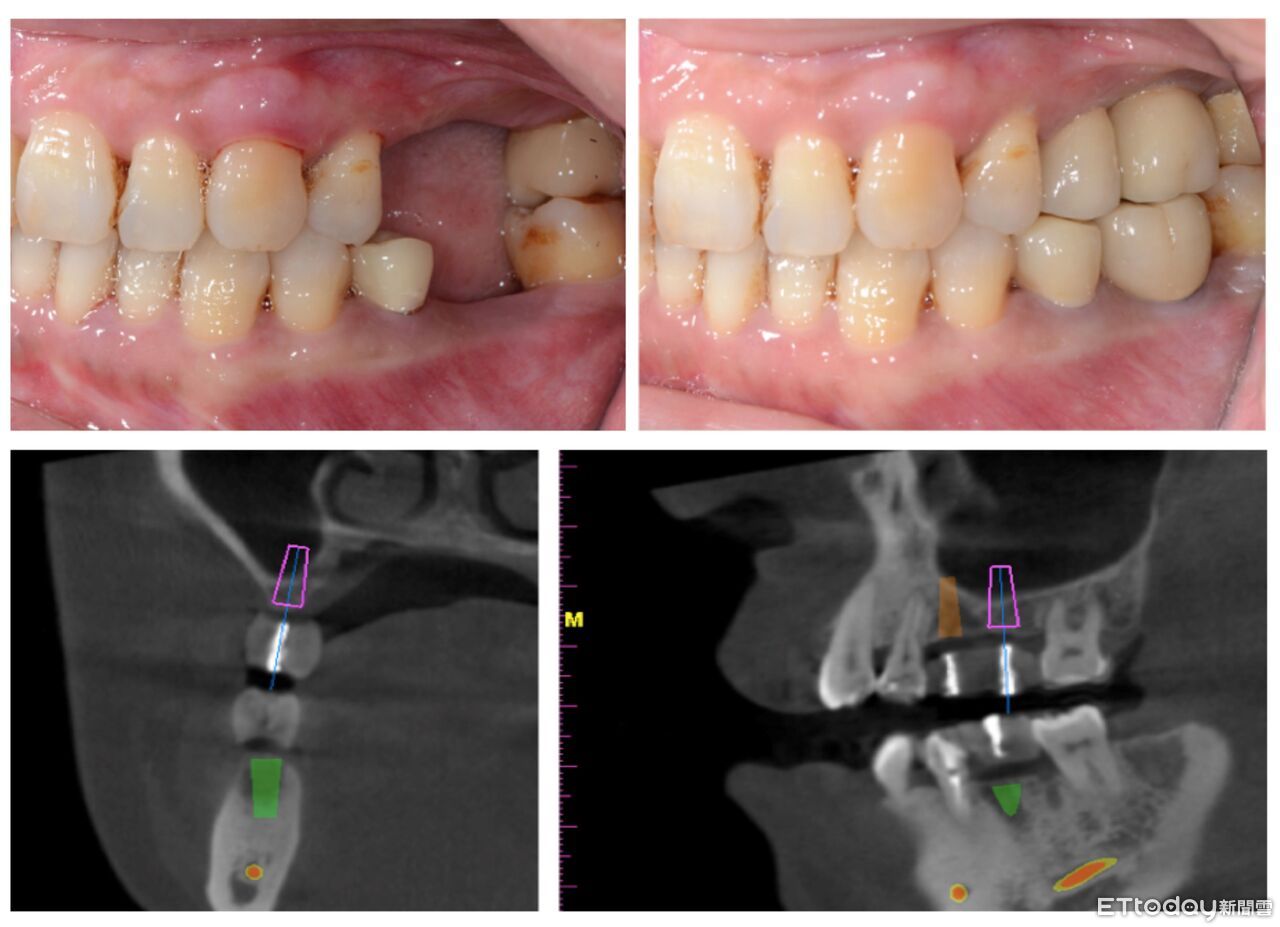

▲透過數位導引規劃搭配數位影像及精準導航系統治療後,最終恢復了完整的口腔功能 。(圖/嘉義基督教醫院提供)

對許多病人來說,最擔心害怕的就是「手術要多久?會不會很痛?成功與否?是否會有牙齦萎縮的問題?」蔡祐年醫師說,隨著數位技術的引進,能在術前先進行3D模擬、規劃植體位置與角度、並透過導引模板輔助植牙,大幅提升手術精確度、大幅縮短植牙手術時間,再搭配數位影像及精準導航系統,不僅減少組織損傷,也降低術後腫脹不適感。牙科的團隊更重視病人的心理狀態,會在術前充分解說,減少焦慮,讓病人更安心。

嘉基牙科團隊備有先進的數位影像設備(CBCT)、3D導航系統及跨科別支援團隊。不僅能協助像王先生這樣的高齡患者,也能處理全口重建或其他困難案例。透過數位導引規劃治療後,最終恢復了完整的口腔功能。